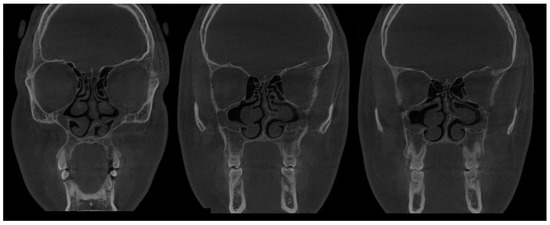

- (1)

- Type 1 SSS (pure SSS = pSSS) (Figure 2) MS four (4) wall retraction, OMC not patent, opacification present;